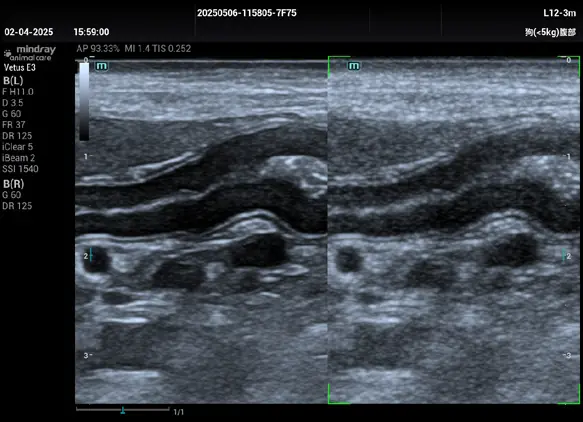

Bu akıllı görüntü işleme teknolojisi, 2D görüntülerdeki parazit (speckle noise) oluşumunu etkin biçimde azaltarak kontrast çözünürlüğünü artırır ve doku sınırlarını çok daha belirgin hale getirir.